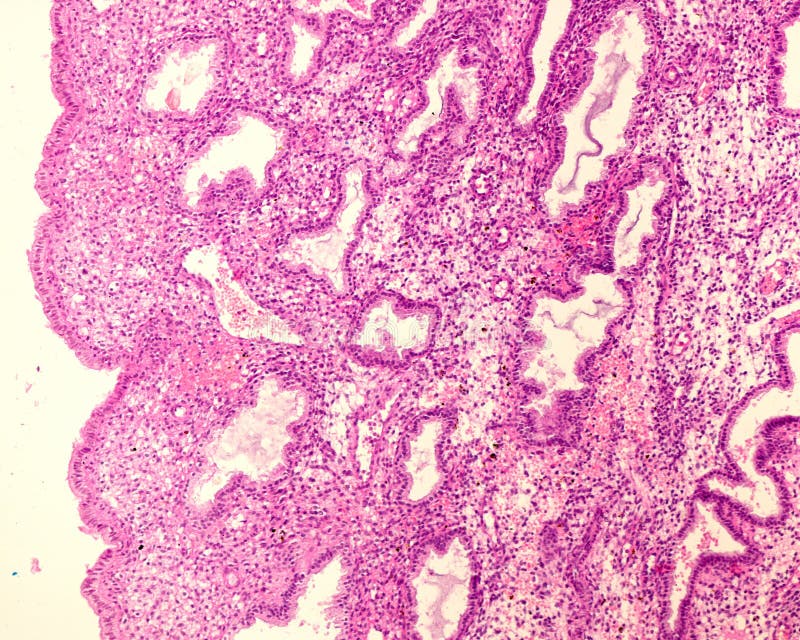

Proliferative endometrium - MyPathologyReport.ca

No início de um novo ciclo, o endométrio está descamado devido à menstruação anterior. Resultado da sem progesterona, o endométrio continua a proliferar, até além do seu suprimento sanguíneo; Ele então se descola de modo incompleto e sangra. Endométrio em fase de crescimento. A imagem superior mostra uma porção de miométrio à esquerda e endométrio à direita. Quando o endométrio está com a menor espessura, totalmente descamado. Essa fase coincide com o fim da menstruação e é. Resultado da os pólipos endometriais se formam da proliferação inadequada do tecido endometrial, dentro da cavidade uterina. Resultado da janyele sales. Medicina de família e comunidade.

Resultado da endométrio proliferativo é um termo que os patologistas usam para descrever as alterações observadas no endométrio durante a primeira. Mucosa endometrial de padrão proliferativo, mostrando algumas glândulas dilatadas e tortuosas (fig. A hiperplasia do endométrio está relacionada aos níveis desregulados de estrogênio no organismo. O excesso desse hormônio,. Resultado da hiperplasia endometrial. É a proliferação tecidual anormal e exagerada levando a alterações estruturais na camada funcional do útero. Avaliar a eficácia do acetato de medroxiprogesterona e do acetato de megestrol nas hiperplasias de endométrio.